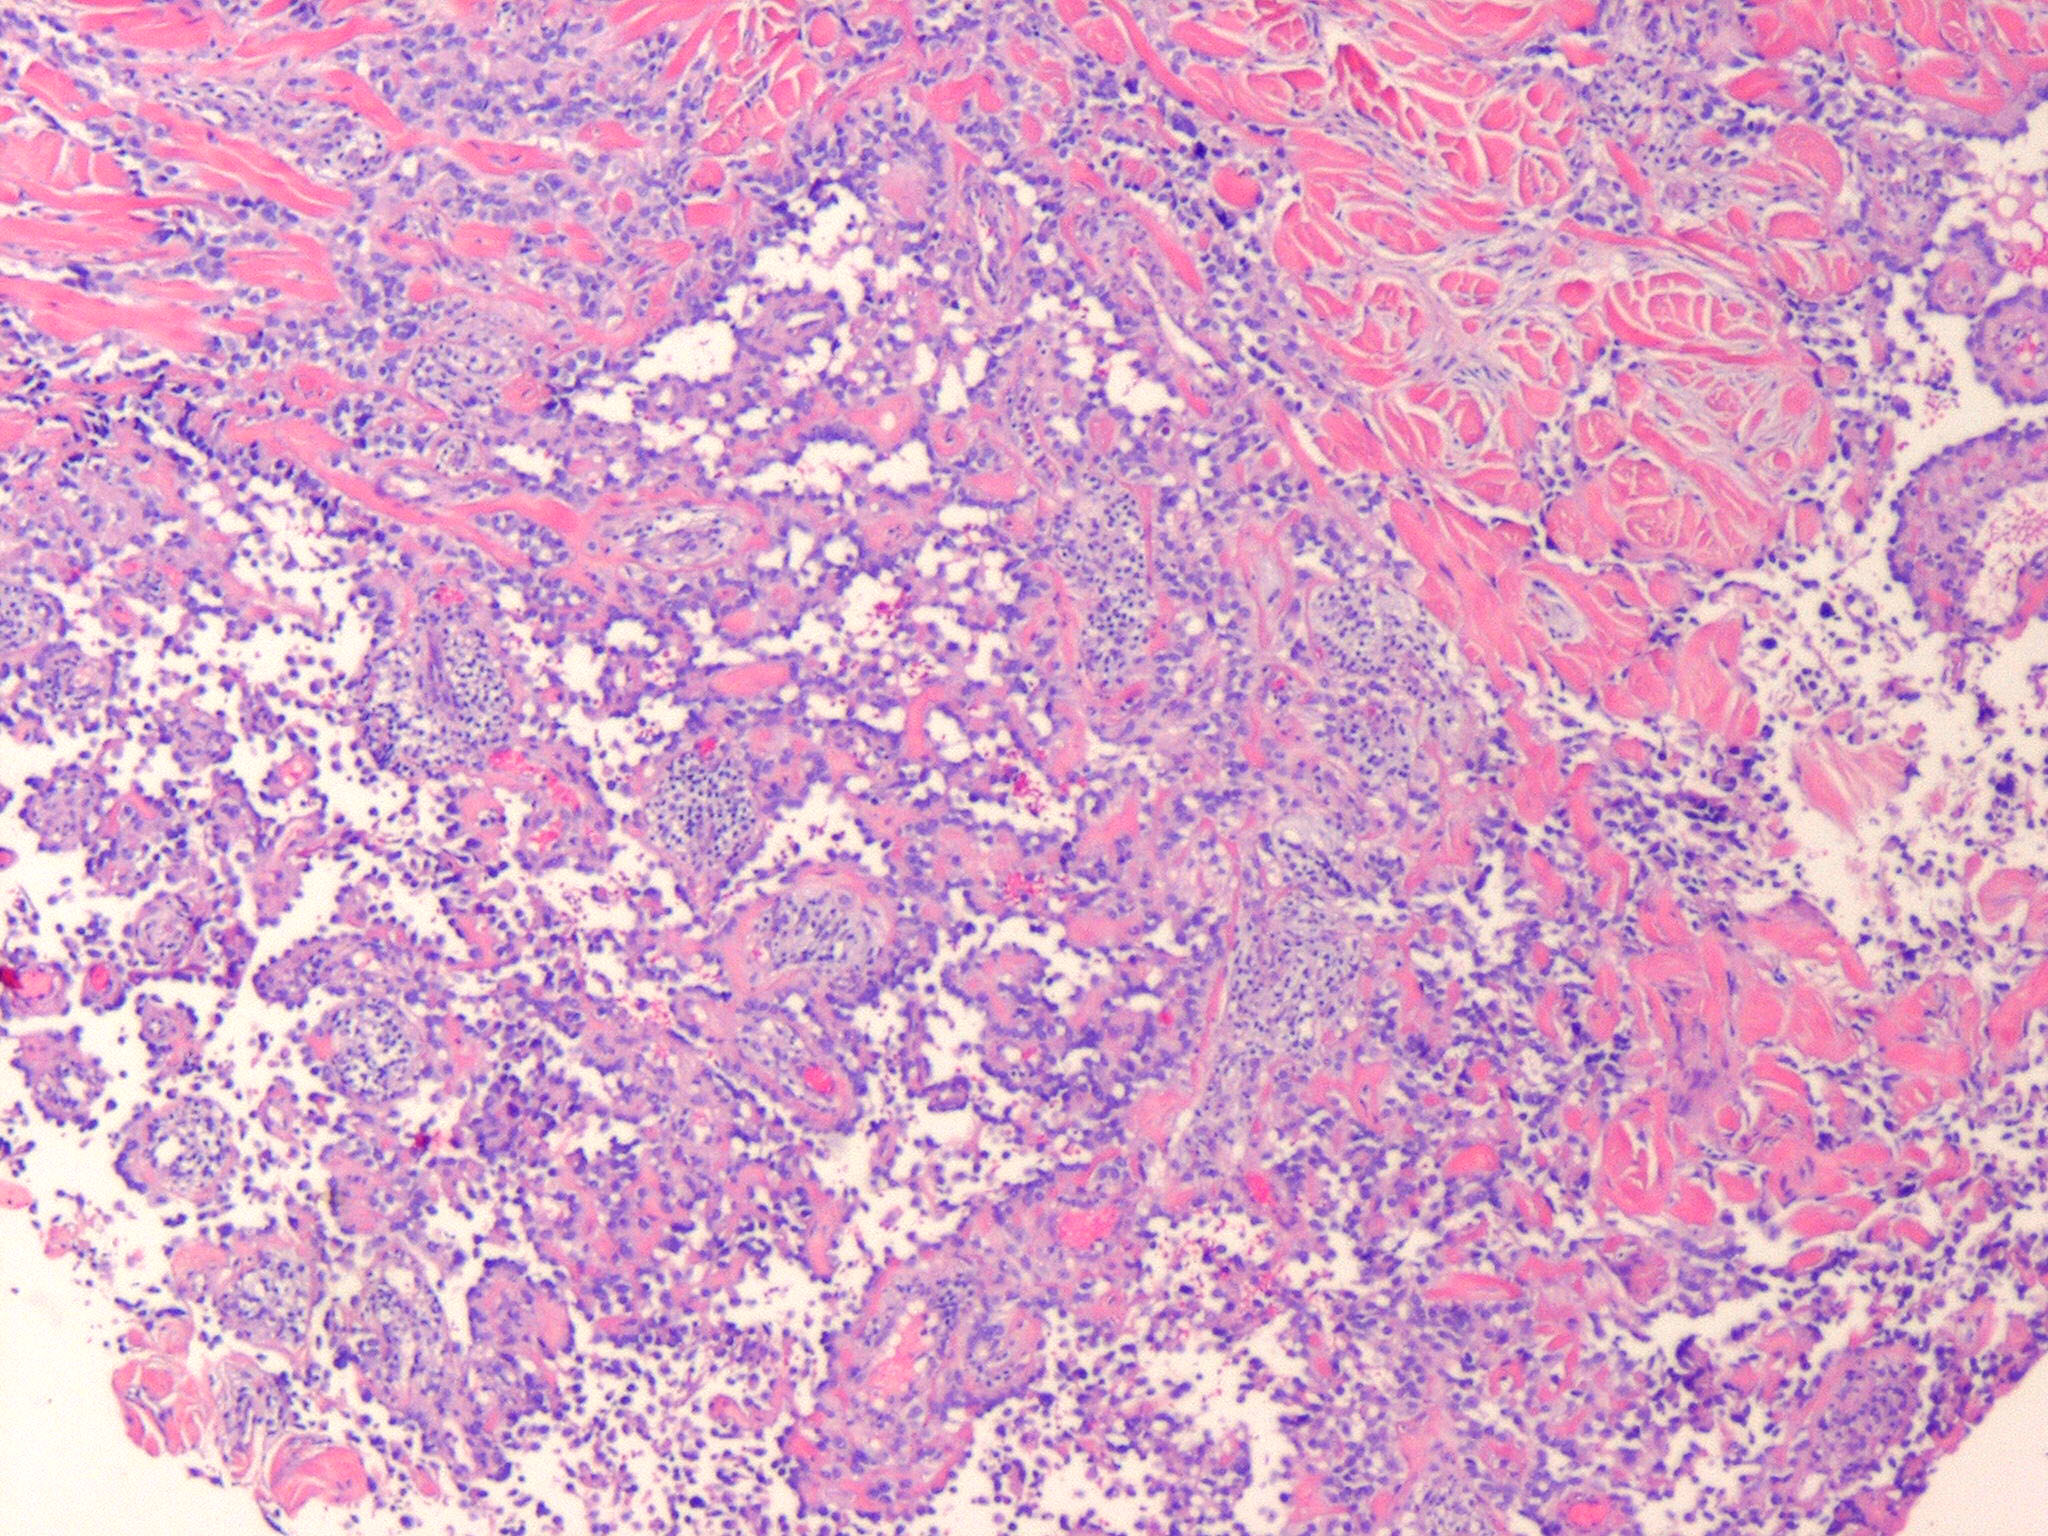

Angiosarcoma = الساركوم الوعائي

OLYMPUS DIGITAL CAMERA